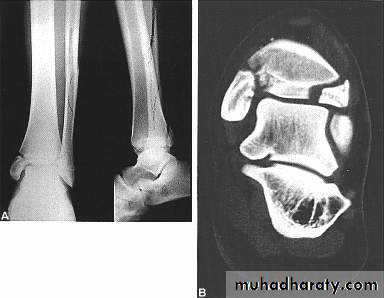

2- CT scan : such as in palvic and spine fractures and in intra articular fracures

When there is a large articular fragment that needs accurate positioning